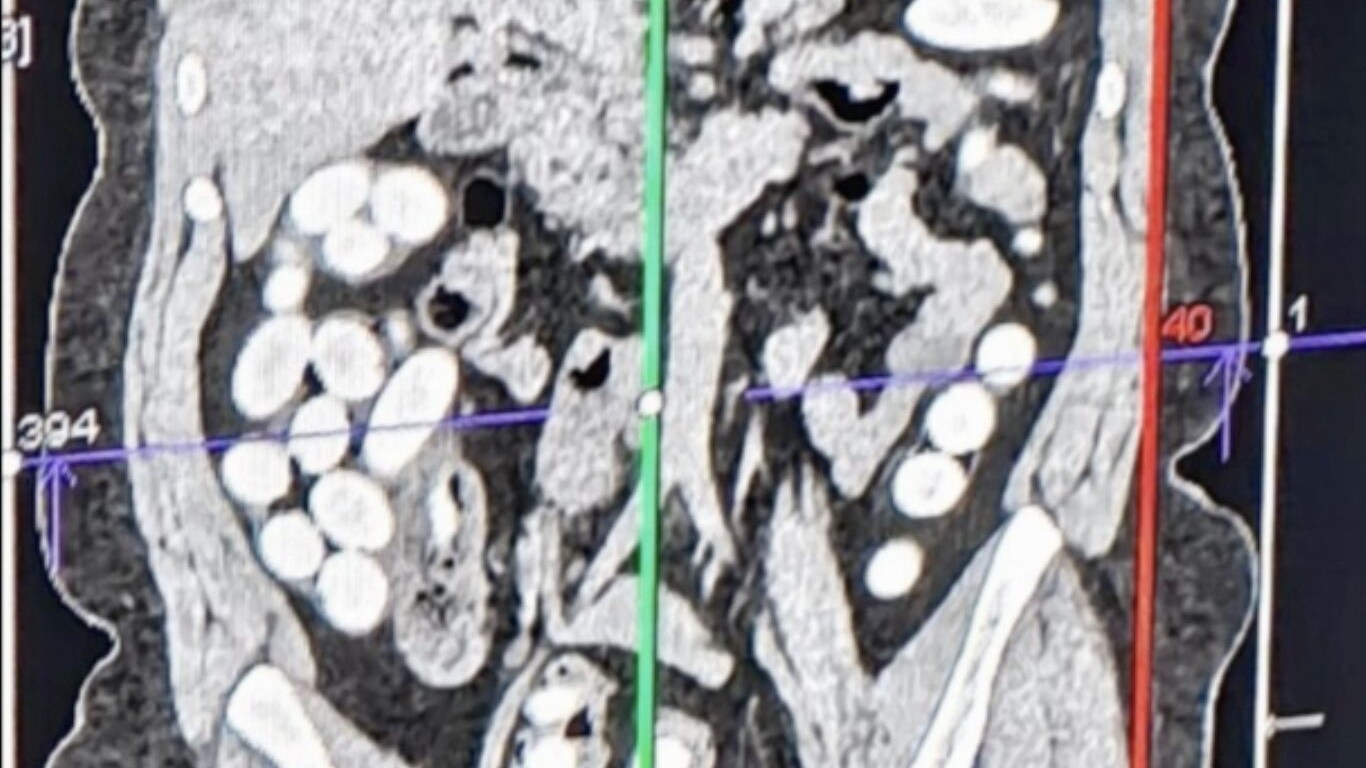

Secondo la dinamica ricostruita dai carabinieri il quarantatreenne, sottoposto a fermo per indiziato di delitto, ha aggredito la sorella durante una discussione nata per motivi non noti e ancora in corso d'accertamento, nei pressi di un complesso di edilizia popolare. L'uomo l'ha accoltellata alle spalle, lesionandole gravamente un polmone. La vittima, ferita, è riuscita ad allontanarsi in auto e a raggiungere casa del suo compagno, nei pressi della quale, ancora all'interno della vettura, è stata ritrovata dai soccorritori. Scattata la chiamata al Numero Unico delle Emergenze 112, sul posto è intervenuto il personale sanitraio, che l'ha soccorsa e trasportata in ospedale, dove i medici l'hanno sottoposta ad una delicata operazione chirurgica, per salvarle la via. Ora è fuori pericolo.